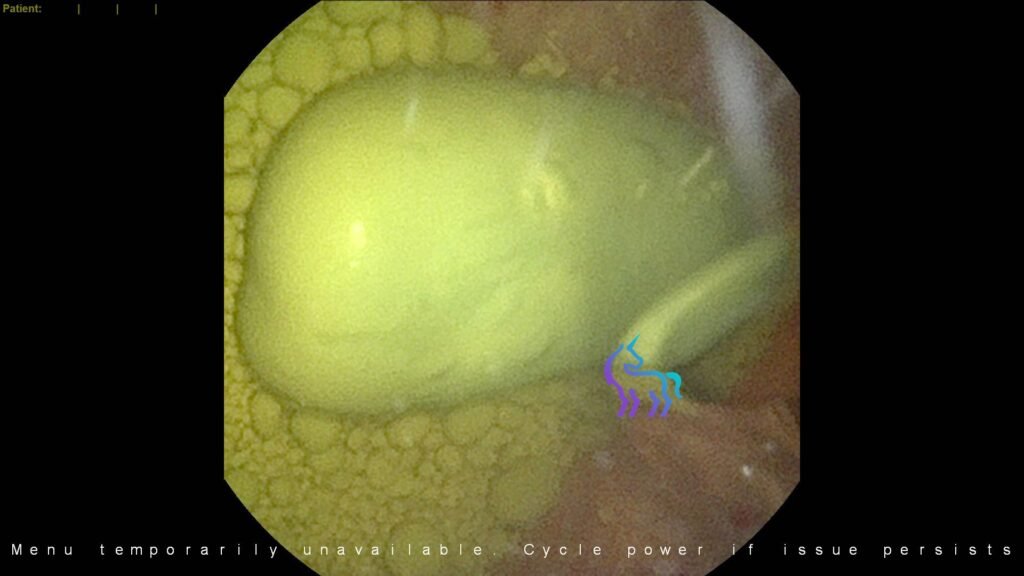

À découvrir : L’endoscopie au service du diagnostic – Cas cliniques Par le Dr P. GHISLAIN Endoscopie et Fibroscopie :